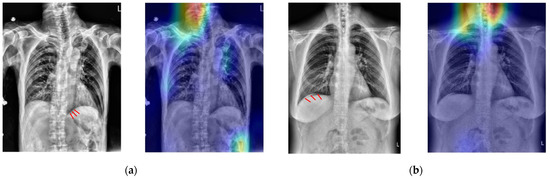

In order to verify if the proposed CNN model uses the correct spatial features to make a decision, Figure 8 shows the Grad-CAM-produced heatmaps of four selected TP cases. In Figure 6a–c, the red regions (higher weights) almost appear on the lesions of PPU. This result implies that all three CNN models could learn the spatial relationship between lesions and the other normal tissues in the X-ray image.

Figure 8. The heat map results of using three different CNNs on four selected TP cases (ad). The red arrows in the first column indicate the lesion. The red areas in the 2nd to 4th columns are the regions where the CNN predicted them as positive cases.